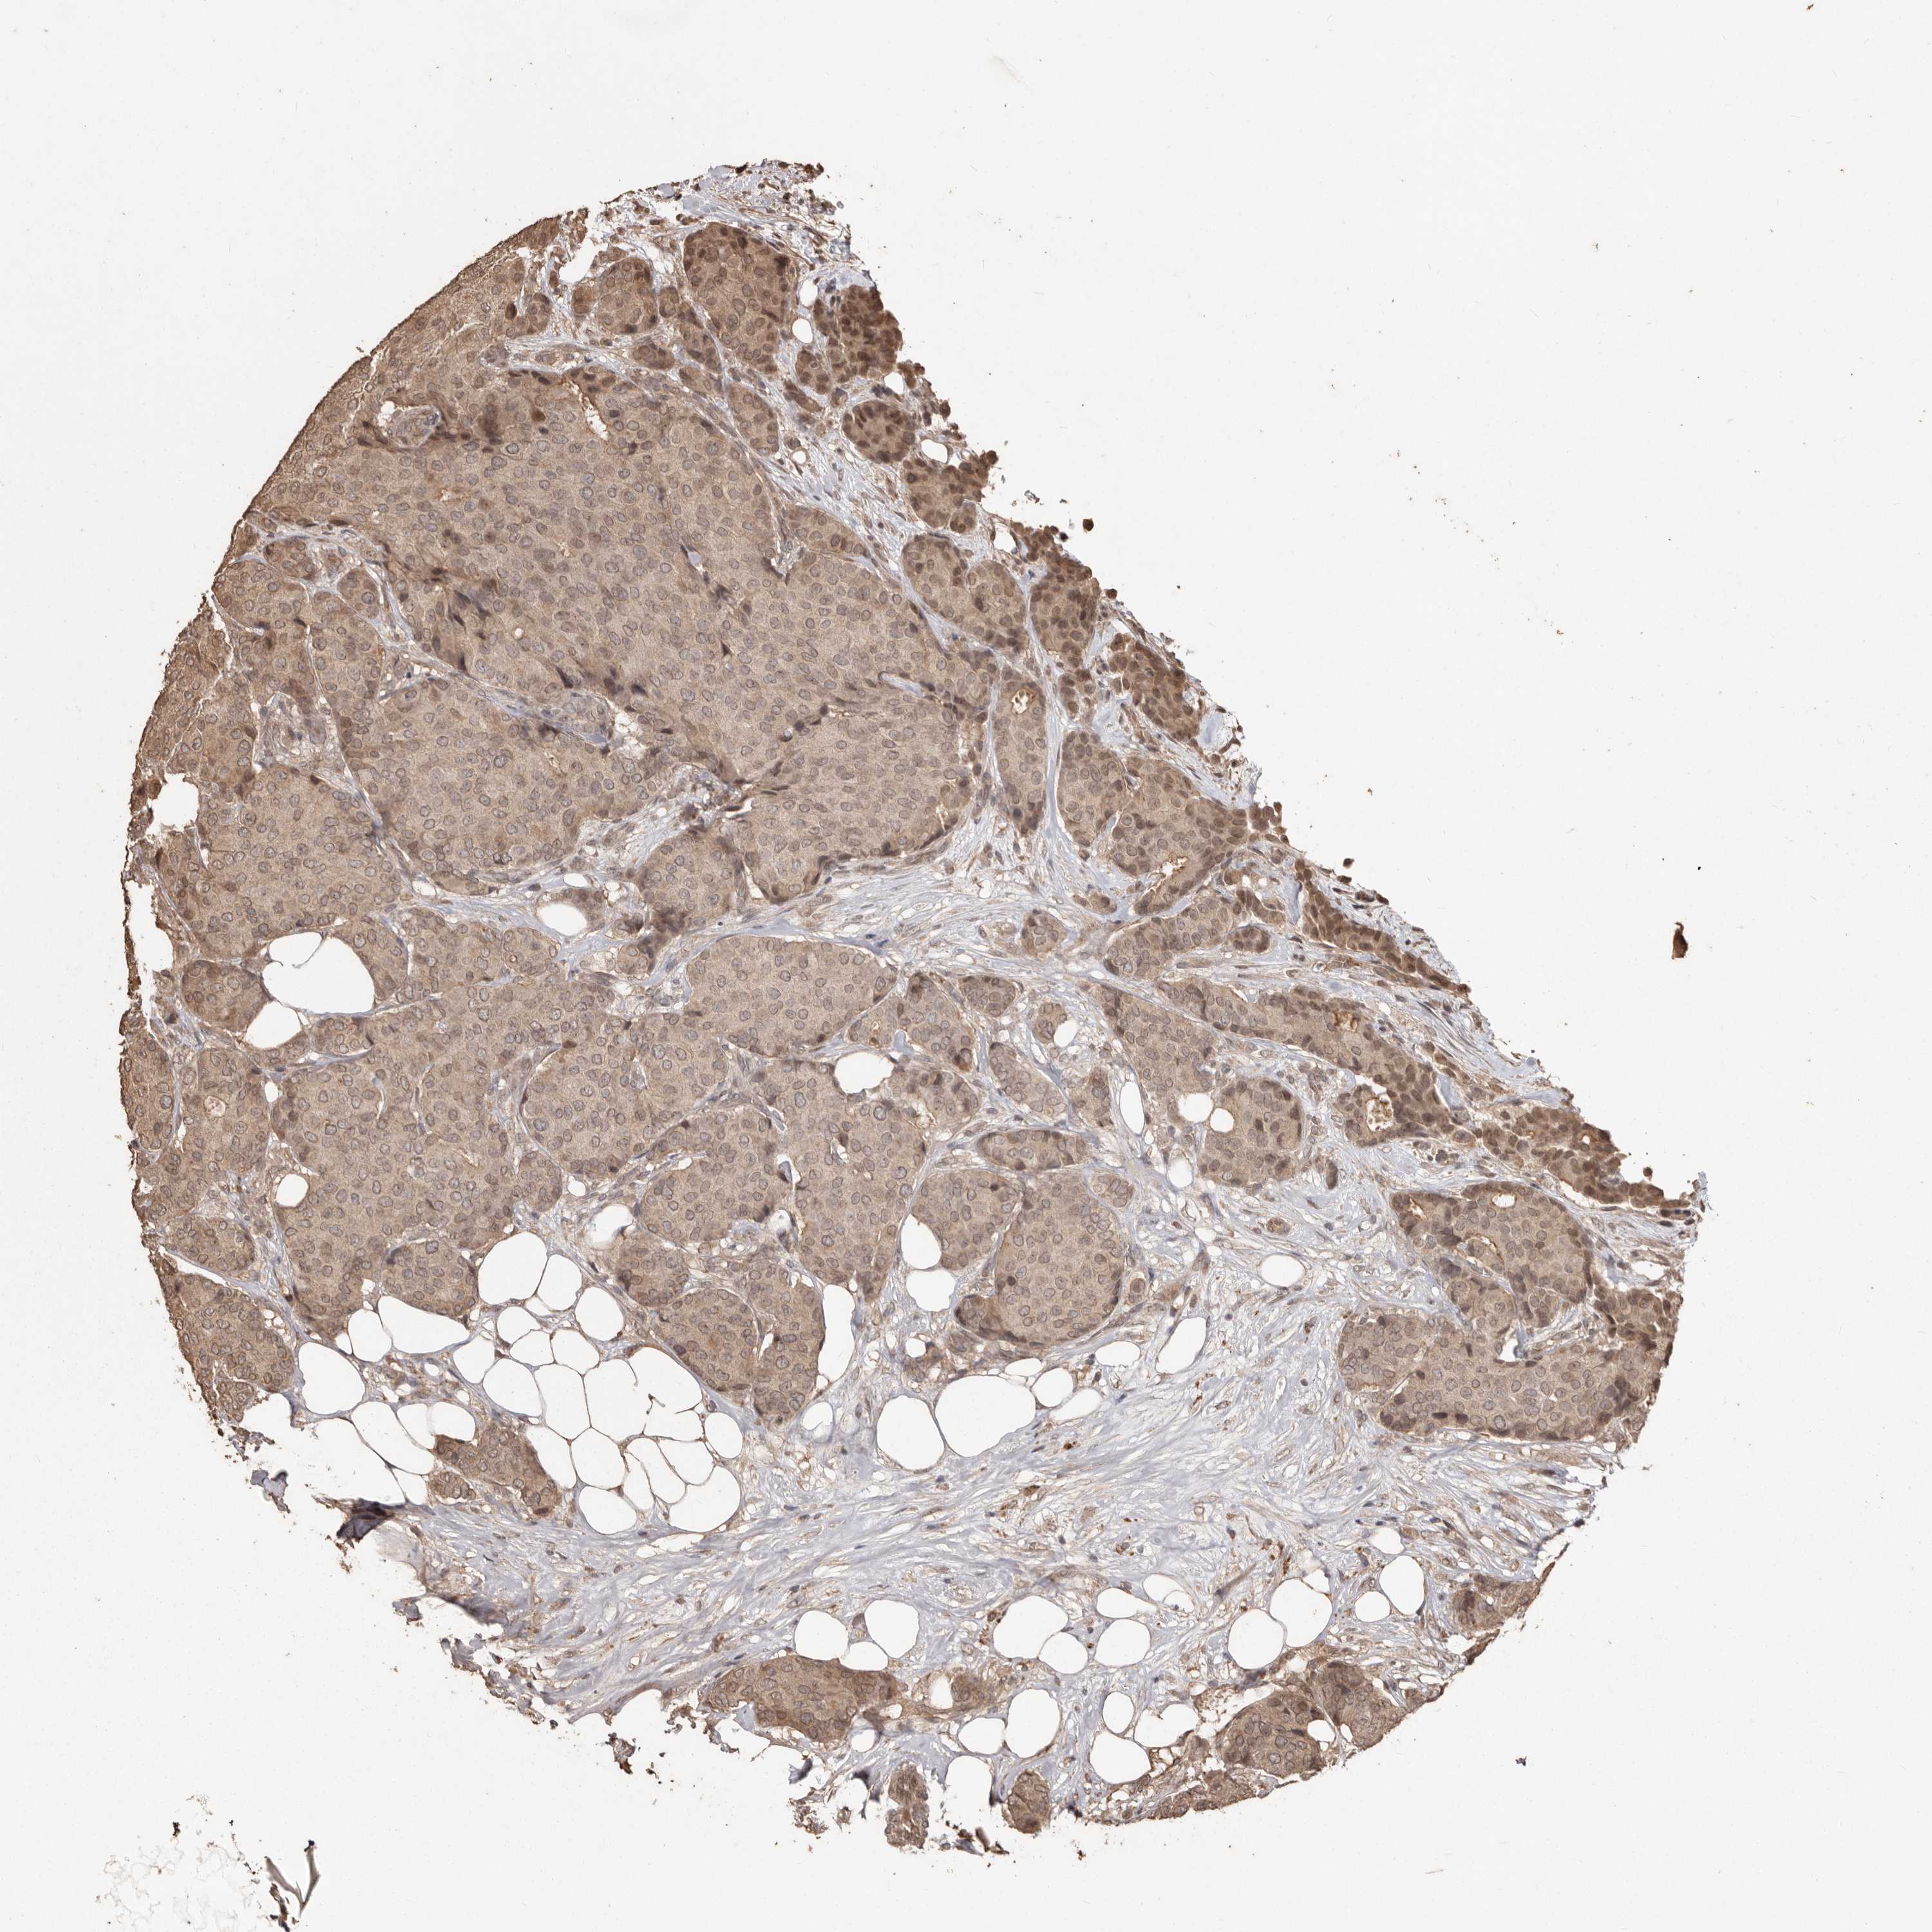

CANCER BREAST CANCER Show tissue menu

BRCA TCGA BRCA VALIDATION PROTEIN EXPRESSION

Breast cancer

Human cancer

Breast invasive carcinoma